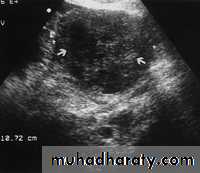

Endometrial adenocarcinoma.

(a) US image reveals a heterogeneous endometrial mass (arrows) that is difficult to distinguish from the myometrium. Cursors indicate the entire transverse width of the uterus.